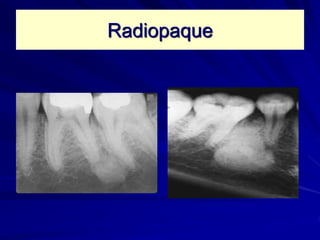

Internal structure

Radiodensity

Radiolucent Radiopaque Mixed (RL-RO)

Radiolucent

Radiopaque

Radiopaque or Mixed

Sunray

Orange peal

Ground glass

Cotton wool

Driven snow

Radiopacities

• Periapical

• Not necessarily

contacting the

teeth

• Multiple

• Generalized